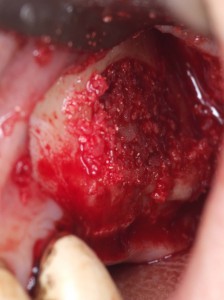

-300x257.jpg) 術中 膿はない 副鼻腔内の感触も通常のサイナスリフトとさほど変わらない

術中 膿はない 副鼻腔内の感触も通常のサイナスリフトとさほど変わらない